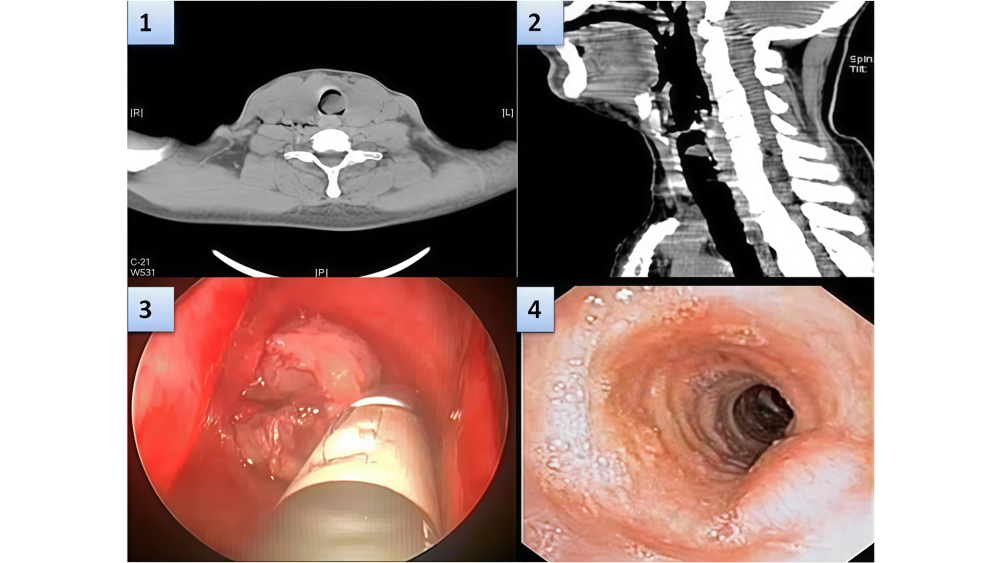

Первичный рак трахеи: редкая, но важная патология в дифференциальной диагностике обструктивных заболеваний дыхательных путей

- Чрезвычайная редкость: Первичные злокачественные опухоли трахеи составляют лишь около 0,2% от всех онкологических заболеваний. Заболеваемость оценивается примерно в 0,1 случая на 100 000 человек в год.

- Основные гистологические типы у взрослых:

✔ Плоскоклеточный рак (45% случаев, наиболее частая форма).

✔ Аденокистозная карцинома (цилиндрома).

✔ Реже встречаются: мелкоклеточный рак, аденокарцинома, саркома.

✔ Важно: У взрослых до 90% первичных опухолей трахеи являются злокачественными. - Диагностическая ловушка: Клиническая картина часто неспецифична и маскируется под доброкачественные заболевания:

✔ Для верификации диагноза обязательны гистологическое исследование и тщательное лучевое обследование (КТ, МРТ, ПЭТ/КТ) для поиска возможного первичного очага в других органах.